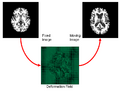

We will continue developping and testing HAMMER registration algorithm implemented using ITK. The goal is to have an initial version ready by the end of the week that can be distributed within NA-MIC community for more extensive testing.

We will develop a Slicer module for the current implementation of the Hammer registration algorithm and test on images from multiple sources to make the algorithm robust and easy to use. Base line results and test will be generated.

- Project week (Boston, 2010): We have 1) extended HAMMER registration algorithm to work on intensity image, bypassing the pre-segment of MR images; 2) replacing the gaussian propagation with the thin-plate interpolation to achieve more accurate and efficient registration; 3) implement the soft-assignment strategy, instead of the one-to-one correspondence, in detecting correspondence during registration.